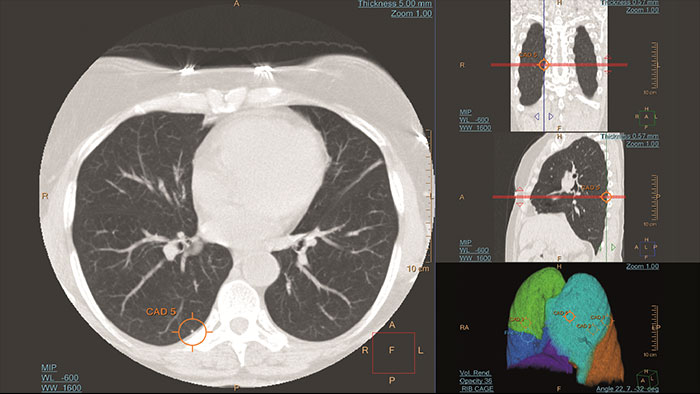

Lung Nodule Assessment (LNA)

CT Lung Nodule Assessment (LNA)

Assessing lung nodules over time

Enables review and analysis of thoracic CT images, providing segmentation, quantification and characterization of physician-indicated lung nodules. The application can be used in both diagnostic and screening evaluations, supporting Low Dose CT Lung Cancer Screening*

Benefits

• Automatic lung and lobes segmentation and one click 2D and 3D nodule segmentation.

• Supports LungRADS categorization, Fleischner Society guidelines for incidental findings as well as a Risk Calculator tool**.

• Pre-filled data including characteristics for each nodule in configurable presets are provided automatically by the application.

• Lung and nodule segmentations can be shared as RT Structures.

* The screening must be performed within the established inclusion criteria of programs/protocols that have been approved and published by either a governmental body or professional medical society. Please refer to clinical literature, including the results of the National Lung Screening Trial (N Engl J Med 2011; 365:395-409) and subsequent literature, for further information.

** Based on patient and nodule characteristics for estimation of the probability that lung nodules detected on baseline screening low-dose CT scans are malignant. These functionalities may not be available in all territories. Please contact a Philips representative for more details.